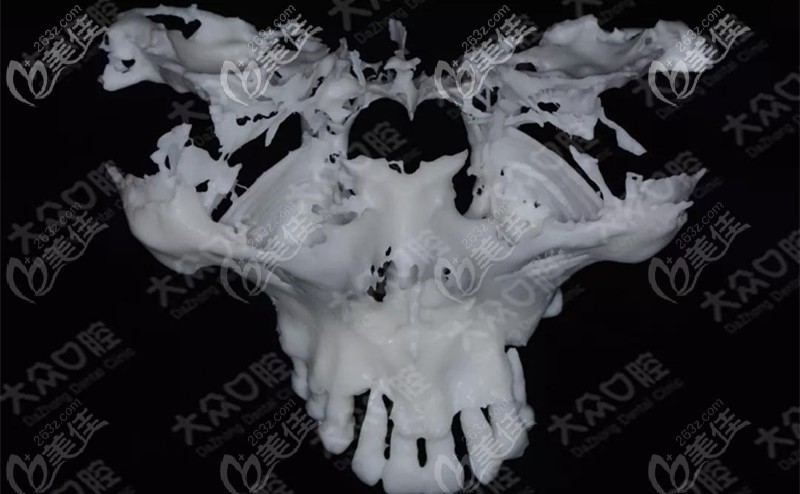

周先略及蒋澍院长为了确保手术能够顺利进行,结合面部CT+光学扫描数据、3D打印顾客上颌骨模型,多次在模型上进行模拟。

▲上颌骨的模型